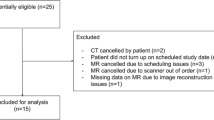

The database search in our Radiology Information System (medavis RIS 4, medavis GmbH, Karlsruhe, Germany) with the search terms: “STEAM” and “postoperative” found 50 patients, 7 of whom were excluded because the interval between surgery and MRI was more than 3 days. Of the patients 43 (21 female) were included with an MRI scan performed within 72 h after surgery. Mean age at the time of MRI was 49 ± 22 years (mean ± standard deviation), range 4–81 years. The average time between end of the operation and the MRI was 37 ± 20 h (mean ± standard deviation, median 41 h).

The T2-weighted TSE in combination with diffusion-weighted images with b = 1000 s/mm2 of (i) EPI and (ii) STEAM of every patient were rated for the presence and severity of air artifacts (AAR air artifacts rating; 0 no artifacts, 1 small artifacts, 2 moderate artifacts, 3 severe artifacts). The rating was done for 3 regions (frontal subdural, ventricular system and resection cavity). Figure 1 demonstrates the rating scale. For further analysis, MRI data were dichotomized for the presence of distorting artifacts in the resection cavity (0–1 without, 2–3 with influencing artifacts).

Susceptibility (air) artifacts rating scale (left T2-weighted turbo spin-echo images, right transversal echo-planar diffusion weighted images, EPI DWI, with b = 1000 s/mm2, arrows resection area with or without T2-hypointense air, stars associated area with or without air artifacts). Air artifacts rating (in the resection area): 0 no air artifacts, 1 small artifacts (e.g. small air bubbles) not affecting more than 5% of the brain tissue, 2 moderate artifacts affecting less than 25% of the neighboring brain tissue, 3 severe artifacts affecting more than 25% of the neighboring brain tissue